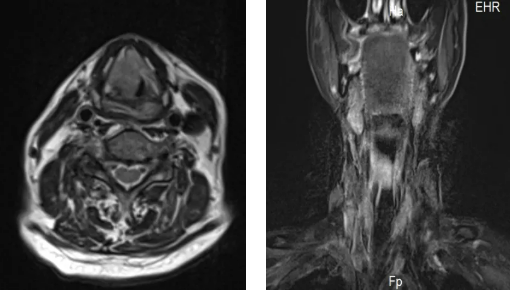

84歲的趙大爺因喉部腫瘤,三個(gè)月前做了氣道改造手術(shù),平時(shí)靠一根氣管套管輔助呼吸。沒想到一天深夜,這根“生命管”突然脫落,頸部的人工氣道口也很快閉合。老人呼吸困難,被家人緊急送往隨州市中心醫(yī)院。

情況萬分危急,趙大爺呼吸急促,只能坐著喘氣,臉色因缺氧逐漸發(fā)青。耳鼻咽喉頭頸外科主任蔡奇山接到通知后火速趕到。檢查發(fā)現(xiàn),原先的呼吸通道已經(jīng)堵閉,必須立即手術(shù)重建氣道。

時(shí)間就是生命。在征得家屬同意后,凌晨的手術(shù)室里展開了一場生命接力。蔡奇山帶領(lǐng)團(tuán)隊(duì)緊急為趙大爺進(jìn)行了喉部腫瘤切除和永久性氣道重建手術(shù)。經(jīng)過四個(gè)多小時(shí)的全力搶救,手術(shù)順利完成。趙大爺?shù)暮粑匦马槙?,脫離了生命危險(xiǎn)。在重癥監(jiān)護(hù)室觀察穩(wěn)定后,他已轉(zhuǎn)回耳鼻咽喉頭頸外科病房繼續(xù)康復(fù)治療,目前恢復(fù)情況良好。